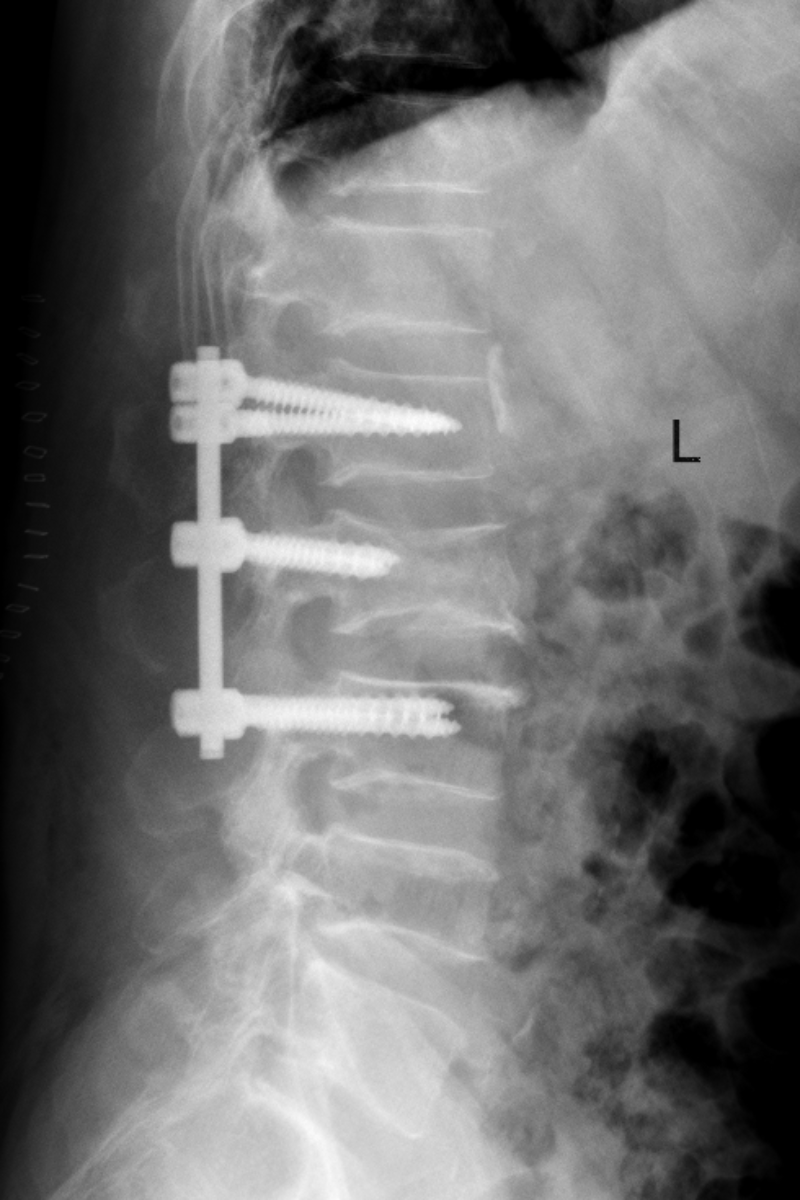

姚仕奮及其團隊與麻醉科主任孫岸靈團隊為廖叔完善術前準備,在麻醉團隊的保駕護航下,于2023年10月20日為廖叔完成了腰2椎體壓縮性骨折后路切開釘棒系統復位內固定術+植骨術,1小時內便完成了手術,術后護士長龍婷帶領團隊為廖叔制定了詳盡的護理方案,指導廖叔康復鍛煉。術后第2天,廖叔在脊柱外科醫護人員的指導下,已可自行下地活動,恢復十分良好,于11月3日順利出院。

這是脊柱外科開科以來的第一臺手術,也是脊柱外科的常規手術之一。每年都有大量外傷患者胸腰椎骨折需行手術治療,脊柱外科的開科,專科化的技術,能更精準、高效的為此類患者進行手術診治。